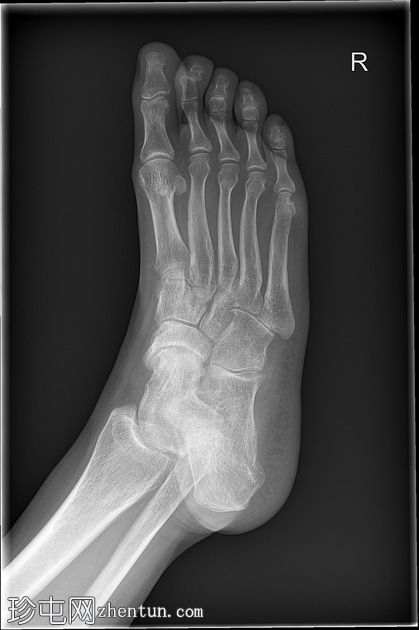

X线片

3.jpg

4.jpg

5.jpg

6.jpg

骨质疏松伴皮质变薄

左侧(正位、斜位)和右侧(正位斜位)第五跖骨头关节旁骨侵蚀

边界不清

局部软组织肿胀